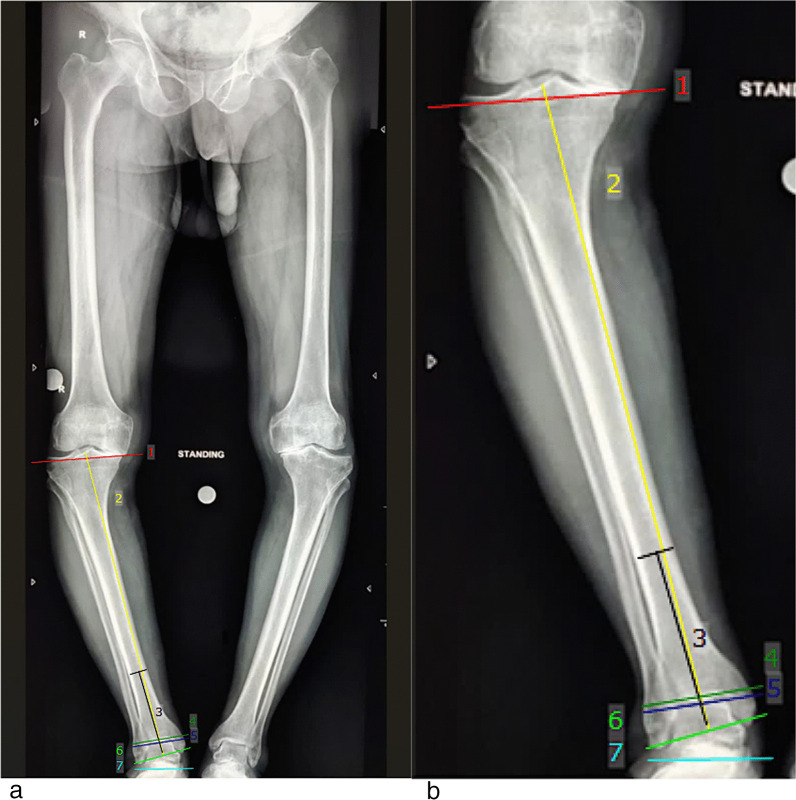

Methods: The prospective observational study included 61 patients (122 knees) undergoing simultaneous bilateral TKA (mechanical alignment). Tibio-talar angle(TTA), tibial Anterior Surface angle (TAS), lateral distal tibial angle (LDTA), talar-tilt angle (TT), anatomical talocrural angle (aTC), ground surface and distal tibial plafond angle (GP), ground surface and an upper surface of talus angle (GT)and tibial plateau and tibial plafond angle (PP) were measured on long-film radiographs to look for changes in the ankle, whereas functional assessment was done using American Foot and Ankle Society (AOFAS), Foot and Ankle Disability Index (FADI), and Forgotten Joint (FJS-12) scores. Patients were sub-grouped based on the Hip-Knee-Ankle (HKA) axis, and the effect of the severity of knee varus on the ankles after TKA was also analyzed. The minimum follow-up was 6 months.

Results: A significant decrease in the tibial plateau-tibial plafond (PP), ground-tibial plafond (GP), and ground-talar dome (GT) angles was noted after TKA (p-value < 0.05). Postoperative functional parameters were comparable to the preoperative status except for FADI, which significantly improved (p-value-0.03). Sub-group analysis based on the severity of knee varus (HKA) revealed GT to be most significantly reduced (p-value-0.036), while the talar tilt (TT) increased (p-value-0.044). Functional outcomes of the ankles clinically improved with the correction of severe knee varus after TKA. At a mean follow-up of 13.2 months post-TKA, 7 out of 61 (11.4%) patients complained of post-TKA ipsilateral ankle pain.

Conclusion: Mechanically aligned bilateral TKA in severe varus deformity of the knee significantly decreases the GT angle but increases the varus tilt of the talus with lateral talar incongruency and under-coverage. Although the acute correction of severe knee varus deformity aligns the tibia more neutrally, resulting in an overall clinically evident improvement in ankle functional outcome, the increased varus talar tilt remains a deep concern.